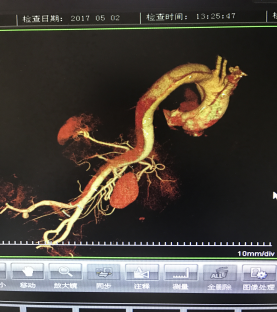

5月2號劉大伯照常早起干活,突然胸部劇烈疼痛,難以忍受,全身大汗,同時伴有右上肢發(fā)涼,他心想這次心絞痛比之前嚴重的多啊,趕緊叫上孩子到吉林國文醫(yī)院心血管內科住院,患者長期高血壓病史,血壓一直控制不理想,大夫給他做了檢查,測左上肢血壓:82/45mmHg,右上肢血壓測不出,心率52次/分,右側肱動脈、尺動脈、橈動脈搏動消失,左側股動脈搏動較右側弱。“糟了,雙側血壓差別這么大,是不是主動脈夾層了?”,接診大夫趕緊找來李主任,李主任反復詢問患者病情,表情突然凝重起來,患者胸痛這么明顯,血壓低的厲害,主動脈夾層的可能性很大。二話不說,李主任立即聯系影像科的醫(yī)生準備做主動脈CTA,移動患者做檢查的過程大夫們非常小心,嚴密監(jiān)測患者血壓變化情況。兩個小時后結果出來了,主動脈夾層從升主動脈一直撕裂到左側髂總動脈?。?!

從開始學醫(yī)到現在已經快9年了,主動脈夾層患者也見過一些,但像劉大伯這種危險類型的還是第一次見到,心里真的為他捏把汗,撕裂的主動脈隨時都有可能破裂,生命隨時可能終止,要知道主動脈夾層的死亡率非常的高,約50%的患者發(fā)病后48小時死亡,約90%的患者發(fā)病1個月內死亡。

李主任詳細的與劉大伯的女兒交代了病情,手術是挽救生命的唯一辦法,為了劉大伯的一線生機,我們積極聯系了我省權威的心血管外科,并做了詳細的匯報,兩家醫(yī)院對此非常重視,為劉大伯開通了綠色通道,安全的把他總到上級醫(yī)院,當天便給他進行血管置換及覆膜支架植術。他術后恢復的很好,后來劉大伯的女兒看望我們,感嘆道:沒想到國文醫(yī)院心內科應急能力這么高,在那么短的時間內診斷明確,才給了我的老父親手術的機會。